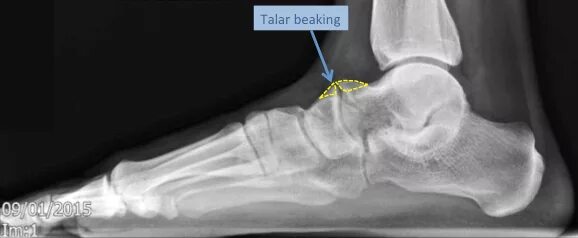

Смещение сустава стопы